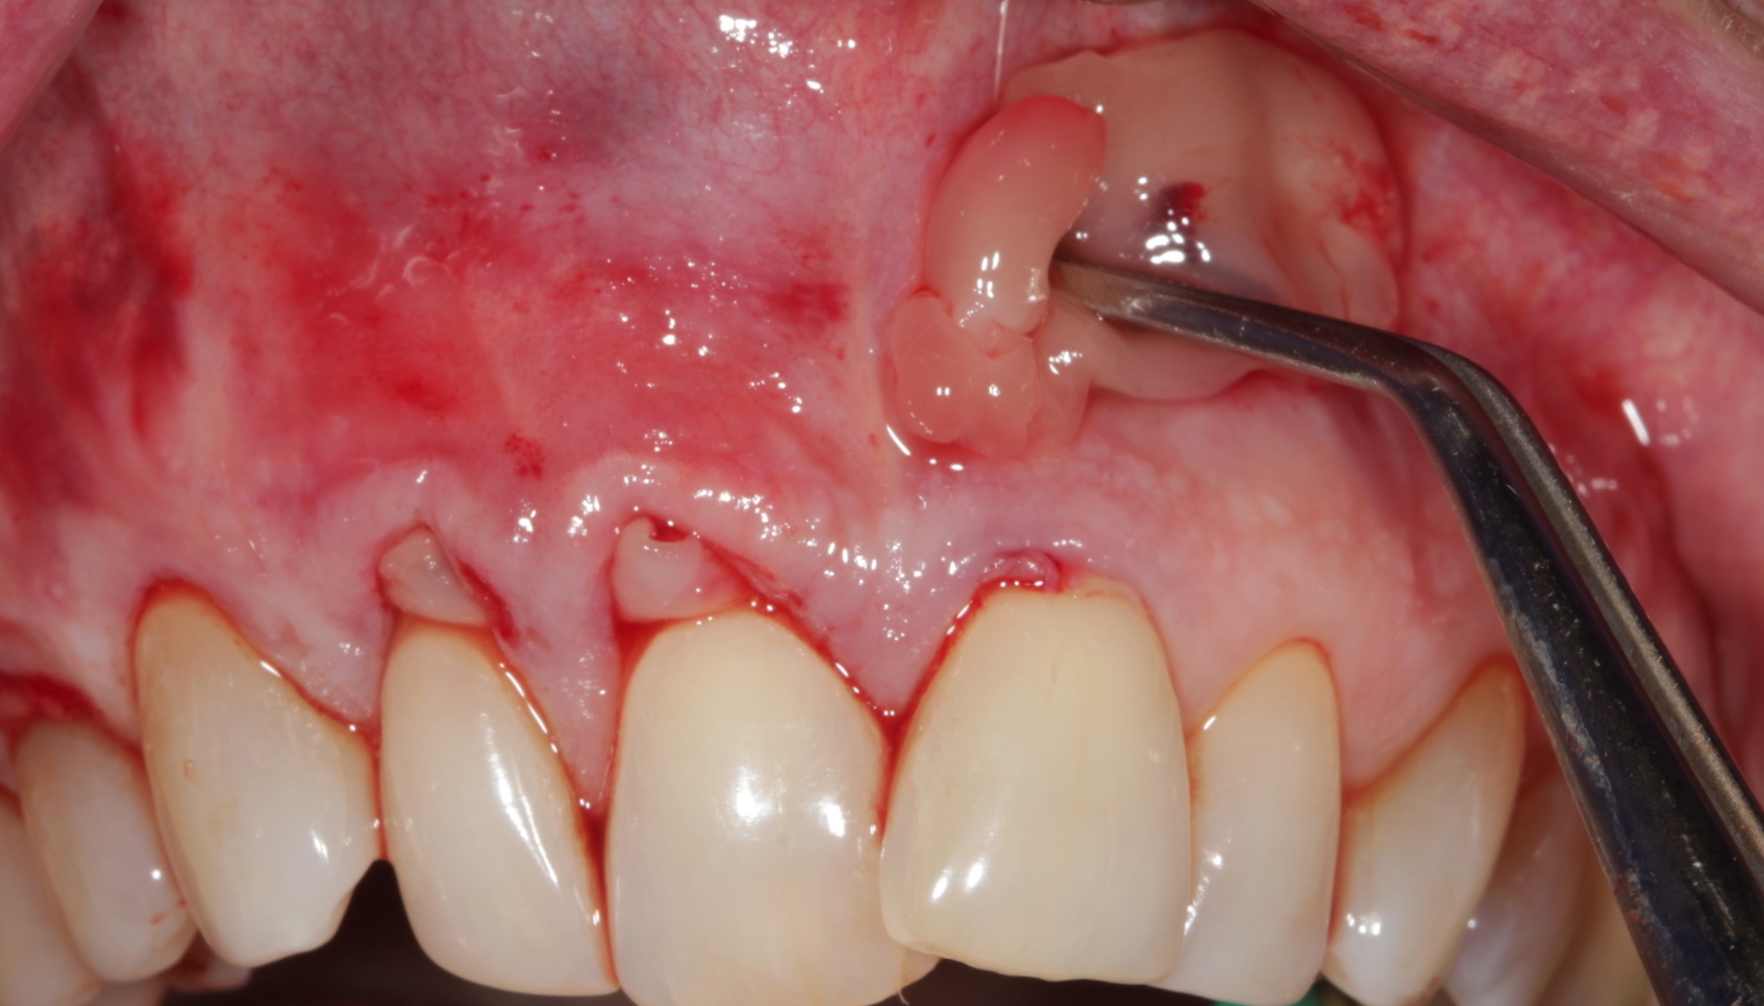

Fig 6. Incision and flap relaxation. A vestibular incision subperiosteal technique-access incision (horizontal mucosal incision) allows for a full-thickness horizontal dissection. A total flap relaxation enables the clinician to avoid uncontrolled flap pressure on the APRF membranes and allows complete and passive coronal positioning of the soft tissues.

Figure 6